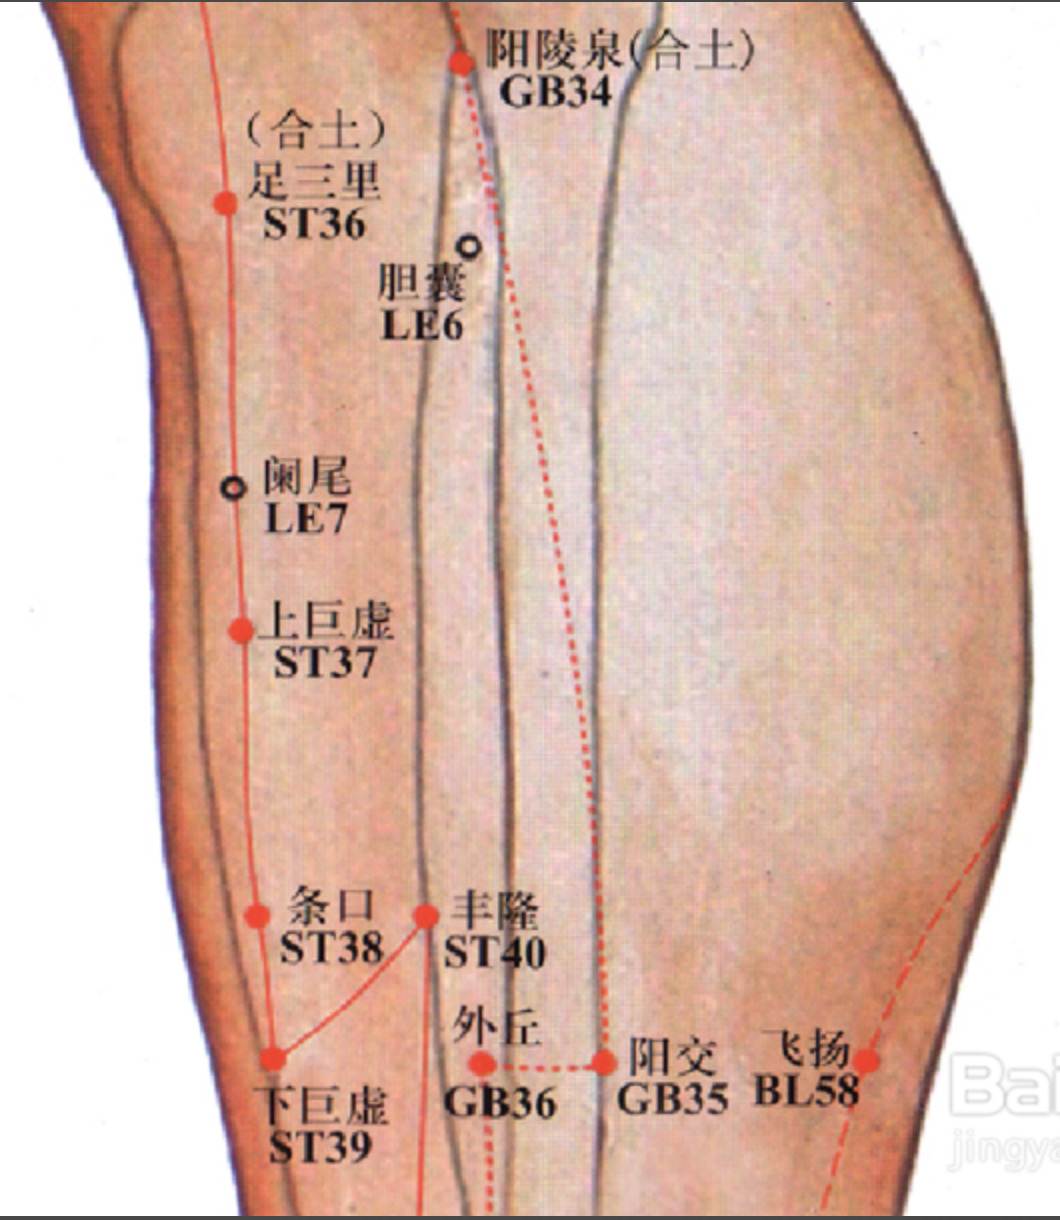

足三里

【定位】 在小腿前外侧,当犊(dú)鼻下 3 寸,距胫骨前嵴(jí)外 1 横指(中指)(图 10-21-4)。

【主治】 胃痛,呕吐,噎(yē)膈,腹胀,泄泻,痢疾,便秘,乳痈,肠痈,下肢痹痛,水肿,癫狂,脚气,虚劳羸(léi)瘦。

【配伍】 配中脘、梁丘治胃痛,配内关治呕吐,配气海治腹胀,配膻中、乳根治乳痈,配阳陵泉、悬钟治下肢痹痛,常灸足三里可养生保健。

【刺灸法】 直刺 1 ~ 2 寸,强身健体用灸法。

【附注】 (1)足阳明经所入为“合”;胃的下合穴。(2)本穴有强壮作用,为保健要穴。(3)参考资料:①据报道,针刺健康人和胃病患者的足三里和手三里,观察发现胃驰缓时针刺收缩加强,胃紧张时变为弛缓,并可解除幽门痉挛。②据报道,针刺单纯性消化不良和中毒性消化不良患儿的足三里、合谷、三阴交,可使原来低下的胃游离酸、总酸度、胃蛋白酶和胃脂肪酶活性迅速升高。③据报道,针刺人及家兔的足三里,发现裂解素(主要是裂解素含有大量多糖体的革兰氏阴性杆菌,也能灭活某些病毒)都有增加,人增加 17.85 单位,兔增加 62.1 单位,两者均在针后 12 小时增加最明显。④据报道,针刺家兔的“足三里”“大椎”可使其调理素明显增加,从而促进白细胞吞噬指数的上升,增强其免疫能力。

丰隆

【定位】 在小腿前外侧,当外踝尖上 8 寸,条口外 1 寸,距胫骨前嵴外 2 横指(中指)(图 10-21-4)。

【主治】 头痛,眩晕,痰多咳嗽,呕吐,便秘,水肿,癫狂,痫症,下肢痿痹。

【配伍】 配风池治眩晕,配膻中、肺俞治痰多咳嗽。

【刺灸法】 直刺 1 ~ 1.5 寸。

【附注】 足阳明经络穴。

阳陵泉

【定位】 在小腿外侧,当腓骨小头前下方凹陷处。

【主治】 半身不遂,下肢痿痹、麻木,膝肿痛,脚气,胁肋痛,口苦,呕吐,黄疸,小儿惊风、破伤风。

【配伍】 配曲池治半身不遂,配日月、期门、胆俞、至阳治黄疸、胆囊素、胆结石,配足三里、上廉治胸胁痛。

【刺灸法】 直刺或斜向下刺 1 ~ 1.5 寸;可灸。

【附注】 足少阳经合穴;胆的下合穴;八会穴之筋会。

胆囊

【定位】 在小腿外侧上部,当腓骨小头前下方凹陷处(阳陵泉)直下 2 寸。

【主治】 急慢性胆囊炎,胆石症,胆道蛔虫症,下肢痿痹。

【刺灸法】 直刺 1 ~ 2 寸;可灸。

阑尾

【定位】 在小腿前侧上部,当犊鼻下 5 寸,胫骨前缘旁开 1 横指。

【主治】 急慢性阑尾炎,消化不良,下肢痿痹。

【刺灸法】 直刺 1.5 ~ 2 寸。